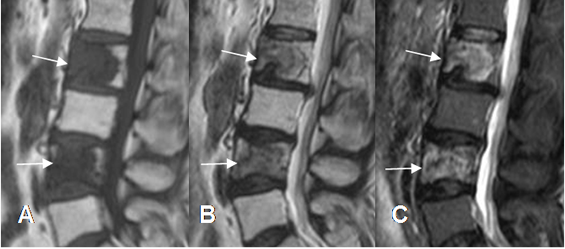

Fig 154 B. Metástasis líticas

A: RM sagital en T2. Lesión neoplásica que compromete el sacro, de señal heterogénea con predominio hipointenso y centro hiperintenso. (Flecha).

B: RM axial en T1 y C: RM axial en T1 con contraste. La lesión compromete el sacro y se extiende hasta el canal medular. Muestra realce heterogéneo, con centro necrótico (Flecha), secundario a lesión metastásica por neoplasia pulmonar.